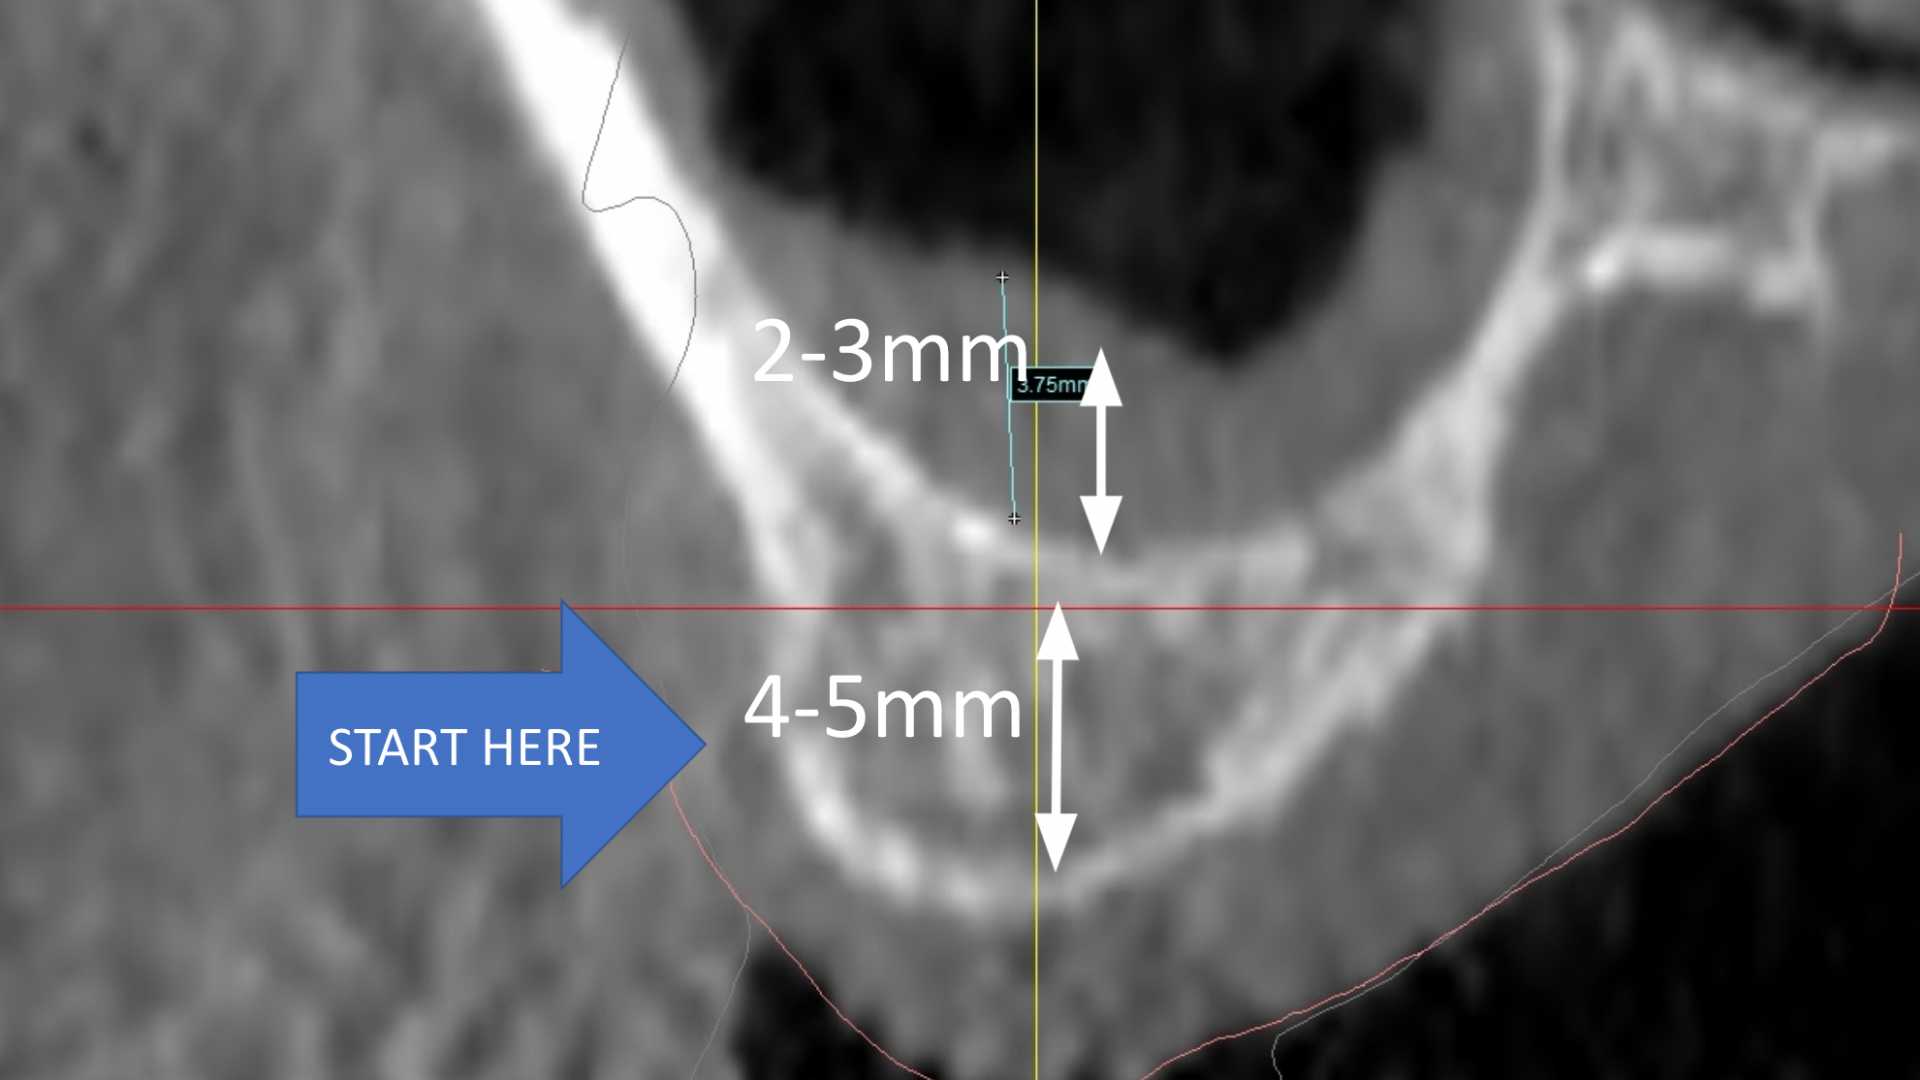

- How to diagnose the exact sinus lift method for each implant patient

- When a crestal sinus lift is indicated.

- When a lateral window sinus lift is indicated

- Gain clarity on sinus anatomy and what to look for when considering sinus lifts.

- Fill out a measurements table to focus on the right data for diagnosis.